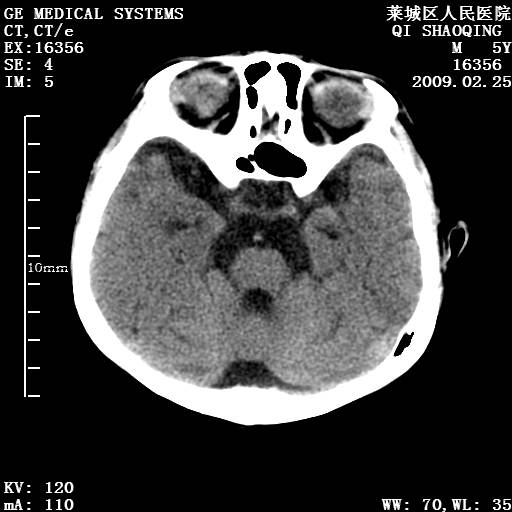

以下是引用wangzhengyuan在2009-2-28 10:22:00的发言:[br]甲状旁腺功能减退引起的脑改变.

以下是引用zsl6918在2009-2-28 10:17:00的发言:[br]首先考虑甲状旁腺功能低下所致,可结合实验室检查明确.另外需除外先天性宫内感染所致.

以下是引用余辉在2009-3-1 9:35:00的发言:[br]患者明显的肢体及智力改变,不支持fahr病,多考虑甲旁低,有可能伴有甲低(呆小症).进一步检查。